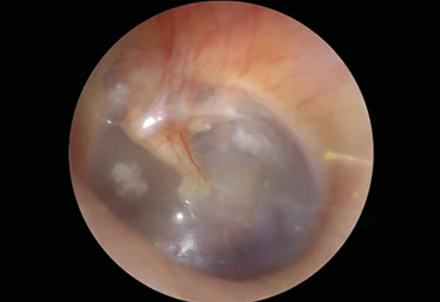

Physical Exam and Video Otoscope

It enables us to examine external and internal ear with video technology. Before using a video otoscope, our professional audiologists conduct a physical examination of your ears. Video Otoscopy enables us to observe the ear canal and eardrum. It proves to be highly beneficial to understand the conditions that affect the ear. Consequently, we become able to suggest a condition related treatment.